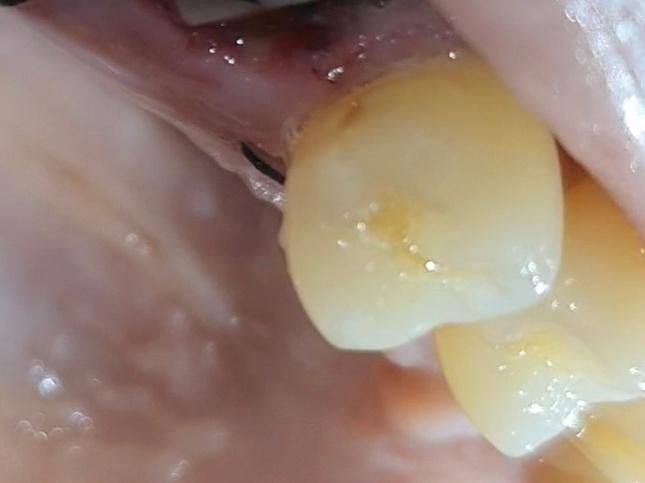

발치한 치아 앞뒤 치아 옆면 충치? 착색?

앞뒤로 치아 옆이 긁힘? 살짝 패여있는데

충치인지 착색인건지...

사진에 보이는건 치아 옆면에 충치가 잇는거 같습니다. 엑스레이 촬영후 치료를 하시는게 좋을것같습니다.

스케일링하면서 주위 착색 제거하고 착색제거후 남은 충치는 간단한 충치치료를 해주시면 좋을거 같습니다. 충치 치료 완료후 연마를 시행하게 되면 치면이 더 부드러워져서 음식물이 달라붙는 현상도 많이 감소할거같습니다. 근처 치과에서 상담후 치료 진행하시면 될거 같습니다.

사진으로만 봤을 경우에는 치아 표면에 작은 충치가 생긴것으로 보입니다. 이런 충치는 간단하게 치료를 할수도 있습니다.

둘 다 충치로 보여집니다. 보통 치아를 뽑고 나면 앞 뒤 치아에 발견하지 못한 충치가 많이 발견됩니다. 현재 상태에서는 특별히 접근이 어렵지 않으므로 간단히 레진 등으로 수복할 수 있는 정도이므로 임플란트나 다른 치료를 하기 전에 먼저 간단히 치료를 하는 것을 권해드립니다.

사진으로 봐서는 좀 애매하고 탐침 등의 기구로 긁어봤을때 긁히면 떼워주면 좋을 것 같습니다 깊은 충치는 아닌 것 같습니다